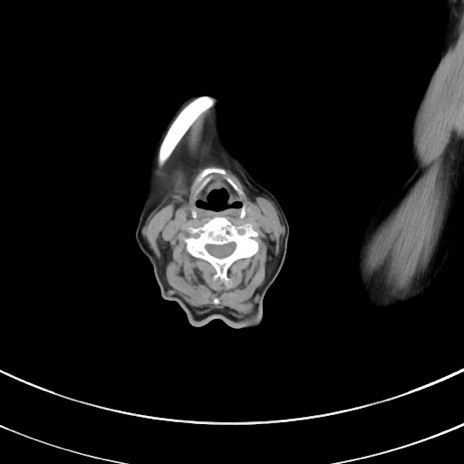

冠状断像